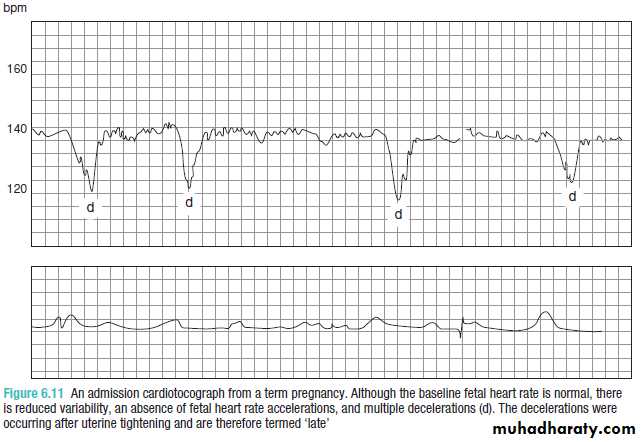

Fetal heart rate decelerations

These are transient reductions in fetal heart rate of 15 bpm or more, lasting for more than 15 seconds.Decelerations can be indicative of

1-fetal hypoxia2-umbilical cord compression.

There is a higher chance of hypoxia being present if there are additional abnormal features such as reduced variability or

baseline tachycardia.

normal antepartumfetal CTG

From the above descriptions, a normal antepartum

fetal CTG can therefore be defined as a1- baseline of 110–150 bpm,

2-baseline variability exceeding 10 bpm3-more than one acceleration being seen in a 20–30 minute tracing.

suspicious features

1-Reduced baseline variability,2-absence of accelerations and

3-the presence of decelerations.

A suspicious CTG must be interpreted within the clinical context.